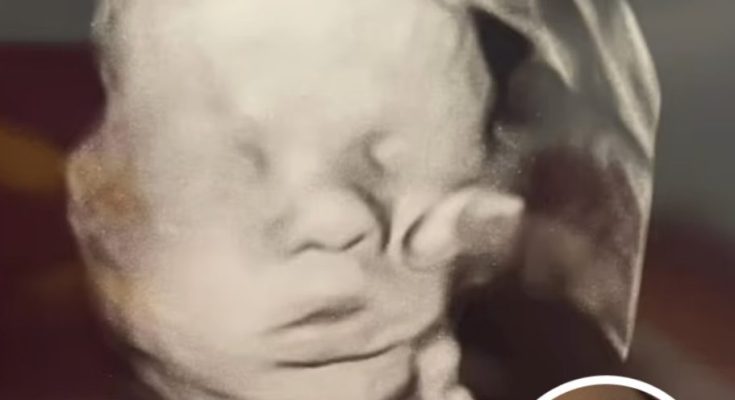

In a moment both tender and mysterious, a Kentucky mother is sharing what she believes to be a direct blessing from above. During her 32-week ultrasound, Amanda Foster, now 33 and eight months along, spotted what appears to be a large hand resting gently on her baby’s head—an image that has since gone viral and been described as nothing less than “a miracle.”

The ultrasound image, shared widely on social media, sparked debates. Many faithful viewers called it “amazing,” others a “miracle.” Skeptics suggested a simpler explanation—that the “hand” was really the baby’s own limb distorted in the scan. But to the Fosters, the message is clear: this is a divine sign of protection following the earlier scare.

“This pregnancy is our miracle continued,” Amanda beams. Daughter Bailey accompanied her to the ultrasound appointment earlier this month, and was the first to exclaim, “Mom, look at the hand!”

Ultrasound of a baby boy with what looks like a hand holding his head, Photo Credit: Amanda Foster/Facebook

“The image brought me to tears of gratitude,” Amanda says, recalling the moment. “I’m beyond grateful for everything God has done—and continues to do—for our family,” she said.